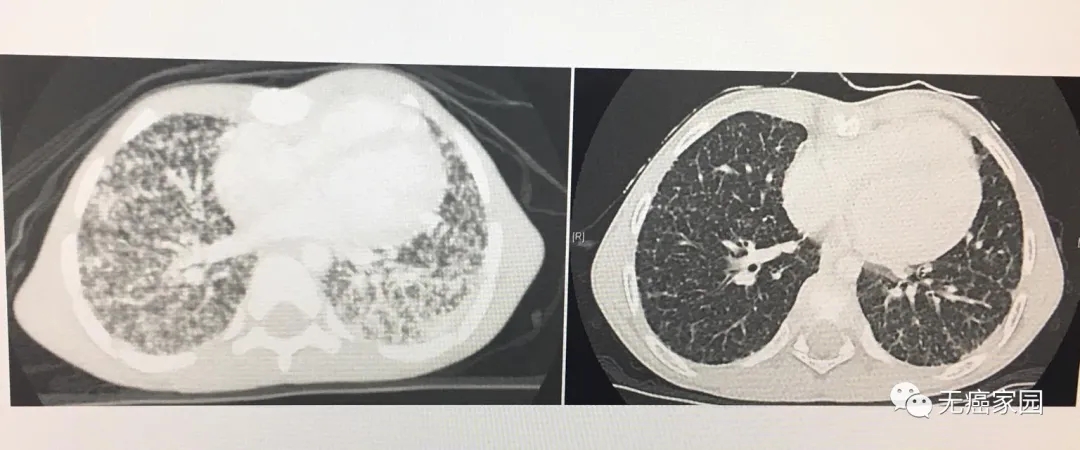

阿什顿5岁时被确诊为4期甲状腺癌,年幼的他接受过手术治疗、放射性碘治疗。但是不幸的是,2017年他用尽了所有的治疗方法,癌症还是扩散到他的肺部、颈部及胸部淋巴结,尽管经历了两轮积极的放射性碘治疗,癌症仍持续存在。他的肺功能受损,需要持续的氧气支持。

他从7月份开始使用该药,就在2个月内,大部分的肿瘤已消失——影像学检查的结果还剩下一些很小的斑点,直到8个月后,阿什顿肺部的肿瘤几乎消失了。他不再需要氧气瓶,已经能够和朋友们一起跑步、一起踢足球。

值得一提的是,这名患有胶质母细胞瘤的女孩年仅3岁,检测出存在NTRK2融合。之前在手术切除病灶后进行全脑放疗,随后接受了14个月的化疗(顺铂+长春新碱+阿糖胞苷+足叶乙甙+甲氨蝶呤+环磷酰胺)。在接受3个治疗周期的repotrectinib后,患儿的肿瘤全部消退,达到完全缓解!

脑部对比增强MRI在筛查时显示额顶病变(红色圆圈)。治疗3个周期后,症状消失,表明完全缓解(CR)